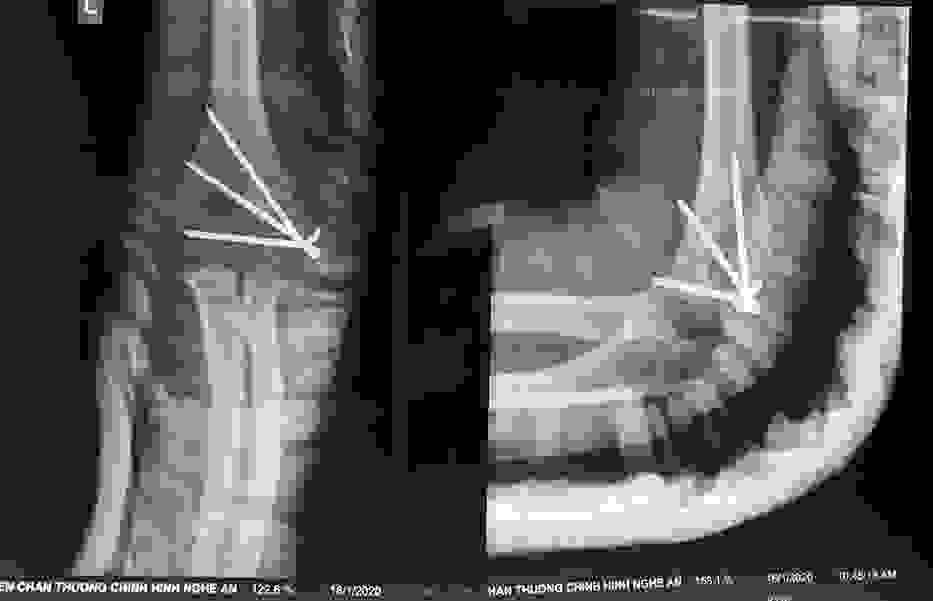

Phẫu thuật thành công ca bệnh hiếm gặp...khớp giả bẩm sinh xương chày

26/06/2019 17:00

Đã xem: 3515

Bệnh viện Chấn thương- Chỉnh hình Nghệ An, vừa phẫu thuật thành công cho bệnh nhi khớp giả bẩm sinh xương chày